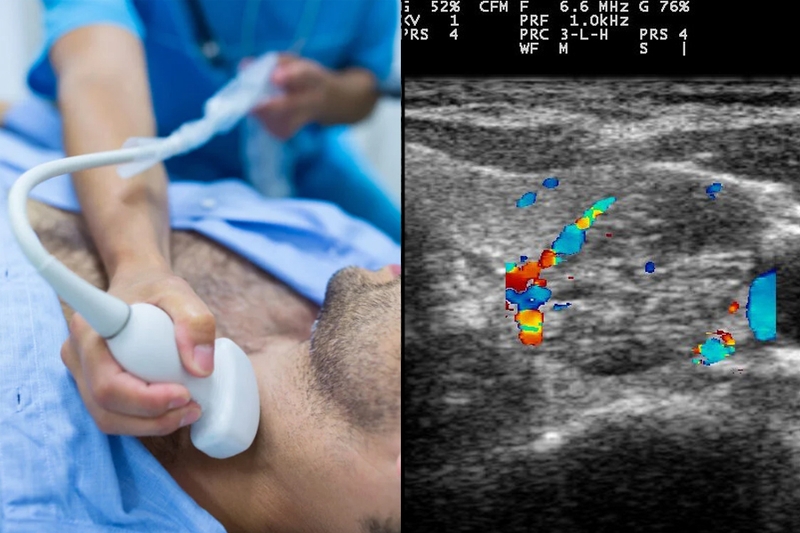

Trước hết, siêu âm tuyến giáp là công cụ nền tảng giúp bác sĩ phát hiện vị trí, số lượng và đặc điểm của nhân giáp như kích thước, hình dạng, đường viền, mức độ vôi hóa hoặc tăng sinh mạch máu. Dựa trên hình ảnh siêu âm, bác sĩ sẽ áp dụng hệ thống phân loại ACR TIRADS để đánh giá và phân nhóm mức độ nghi ngờ ác tính của nhân giáp.